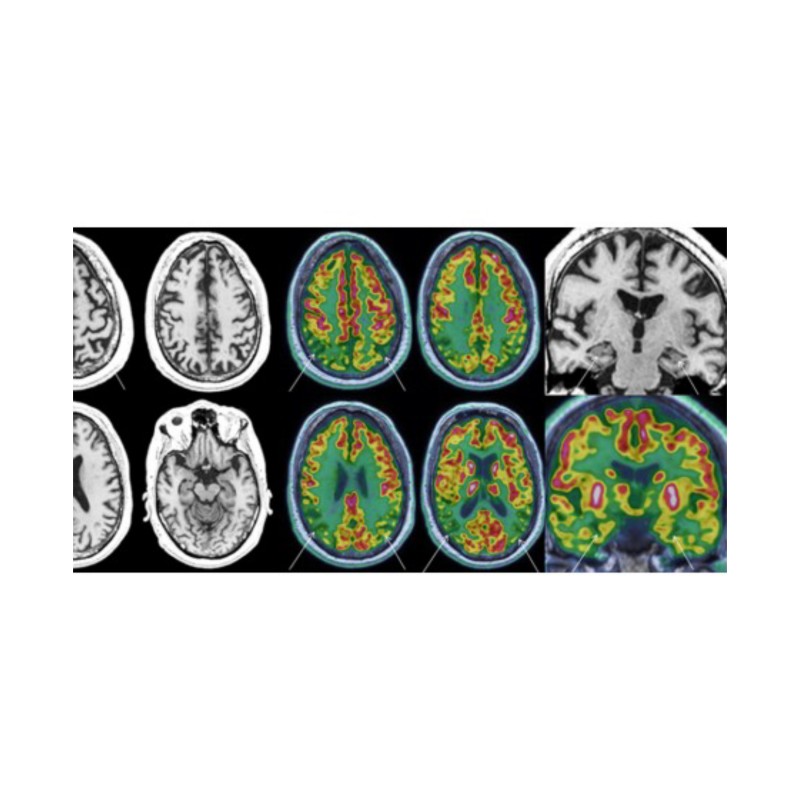

La neuro-imagerie Agrandir l'image

LA NEURO-IMAGERIE

Plus qu’un simple outil de cartographie vers un bilan cérébral

La neuro-imagerie a été longtemps un outil d’exploration de choix pour les recherches en neurosciences. Dans cette conférence, nous tenterons de comprendre en quoi l’étude des images a pris une place importante dans l’évaluation de la santé du cerveau.